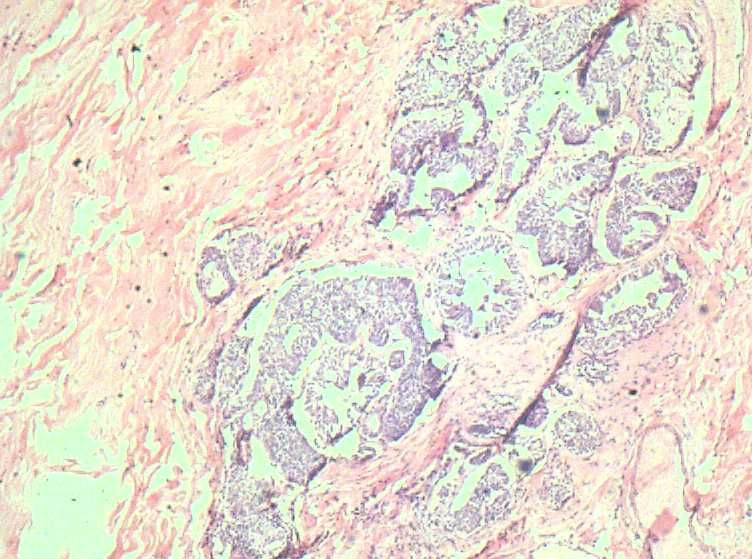

女41岁,左腺包块。肉眼:不整形囊壁样组织,大小2*1.6*0.3CM,壁厚0.1—0.3,未触及结节,未见出血及坏死。

• 乳腺积乳性包块?图1

图1

似乎有导管扩张、慢性炎细胞浸润、大汗腺化生、普通型导管增生等病变,没有看到囊壁内衬上皮或囊壁结构。

这例报了 慢性囊性乳腺病。不知可否?

乳腺腺病伴普通型导管增生

报乳腺增生性腺病伴导管上皮不典型增生。

。图12-16可以看到导管上皮异形增生(导管上皮极向紊乱)